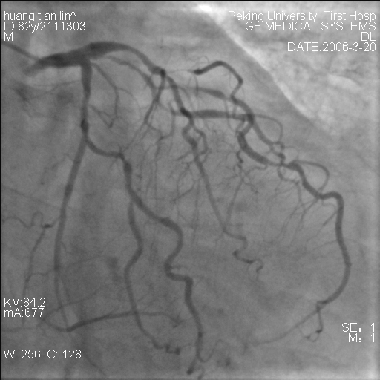

遠(yuǎn)端保護(hù)裝置在急性心肌梗死中的應(yīng)用(圖)

遠(yuǎn)端保護(hù)裝置在急性心肌梗死中的應(yīng)用